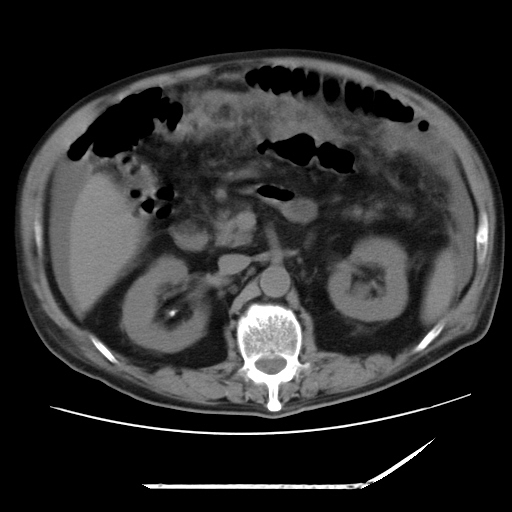

以下是引用zxl51642在2009-8-12 18:55:00的发言:[br]1、肠系膜脂肪浑浊,密度增高,腹水,支持腹膜炎诊断;2、右肾盂及输尿管中段结石,左输尿管起始段结石;3、胆囊切除术后改变?4、双侧胸膜腔少量积液;5、胰腺体积不大,勾勒清楚,肾前筋膜无增厚,不支持胰腺炎,请结合血尿淀粉酶及临床。